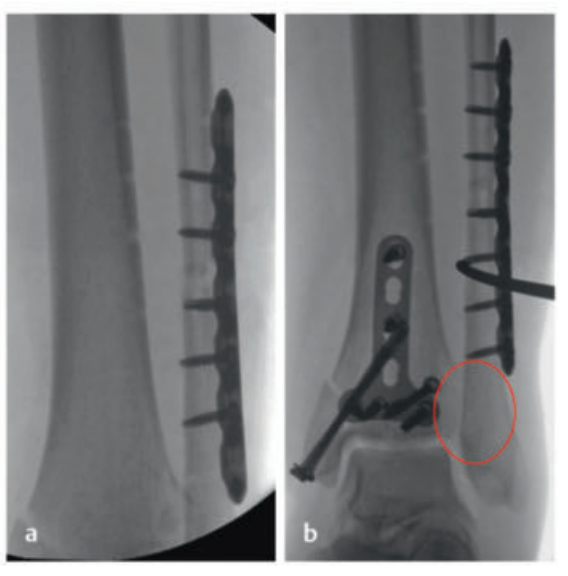

微创手术(小切口入路、经皮螺钉固定、插入式接骨板)可与切开复位技术良好结合。根据骨折形态,可能需要采用关节镜辅助手术。术中三维影像导航技术也应常规用于术中监测。

待软组织状况改善(出现 “皮肤皱纹征”)后,开始对患者进行手术治疗,首先处理腓骨(遵循 “先处理腓骨” 原则)。术中检查发现韧带联合存在不稳定情况。

术中临床图像显示了损伤的严重程度,同时体现了微创手术技术的优势,以及在必要时下胫腓联合切开复位重建的重要性。借助斯氏针的 “操纵杆(Joy-Stick)” 技术,可显著简化关节面的复位操作。